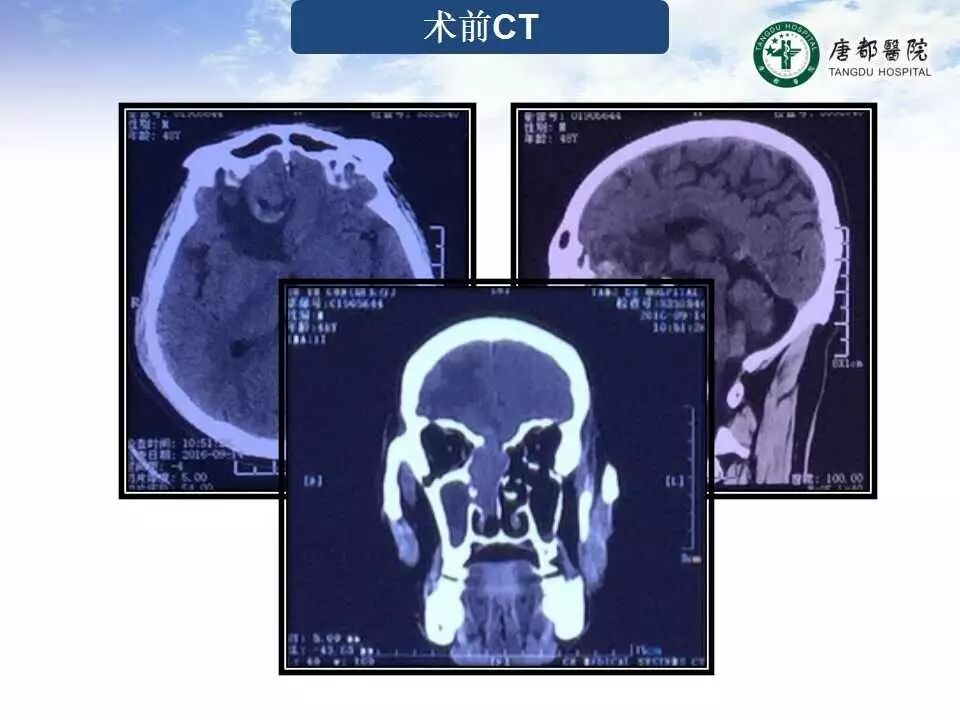

Case 2

长按并识别二维码即可查看该手术视频